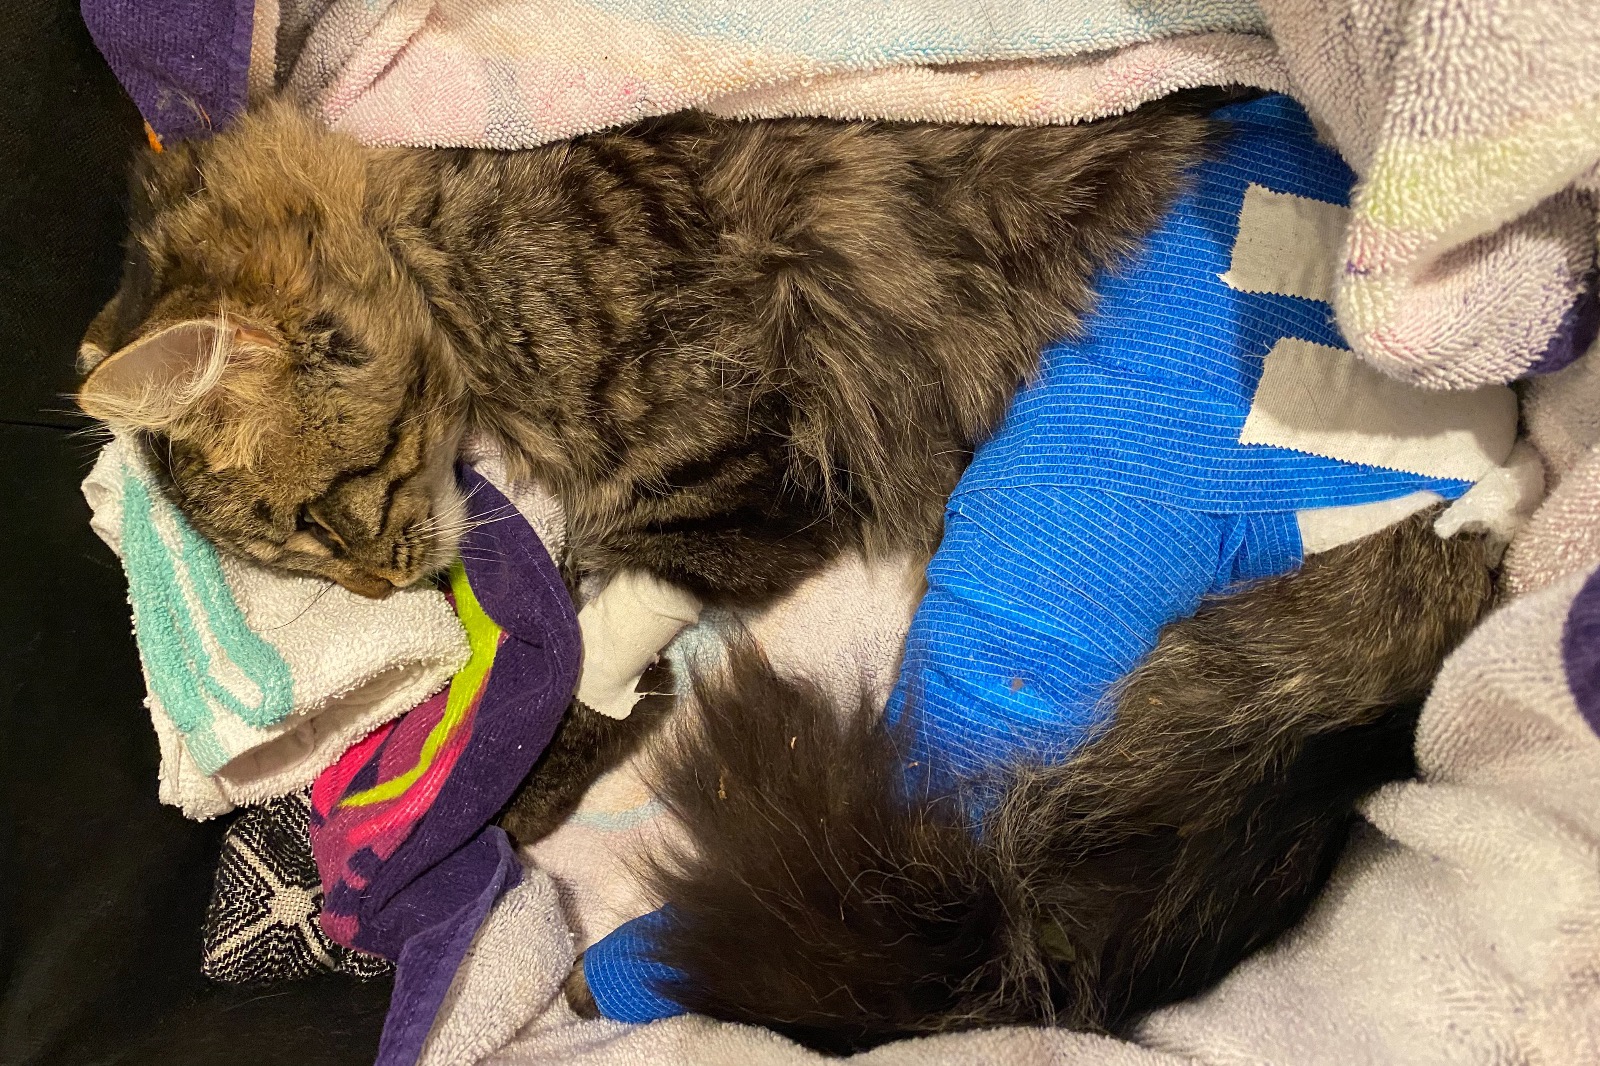

He had been hit by a car. Kitty was almost lifeless. his breath was shallow and deteriorating, his eyes were rolling while his left hind leg was dangling. I ran to my husband (who was giving our 19 month old twins a bath) we stealthy packed up the car and drove to the closest veterinarian hospital. The doctor sedated him to get x-rays and to relive the pain. After the X-rays his vitals were taken. His temperature had dropped so severely the vet urgently wrapped him up in heating blankets and hooked him up to fluids. Doc fed him some vitamins and glucose through the IV to keep him going. The radiography showed no visible signs of internal bleeding but the blood test told a different story. Although he wasn't bleeding internally, the diagnostic test showed that his liver and kidneys were struggling to preform from the impact of the car, not catastrophically enough for emergency surgery but enough to cause concern. He hasn't been able to urinate since and we've been taking him into the vet to relieve his bladder while we await surgery.

As for the X-ray results, we were informed that his femur had shattered into 7 pieces and that the trauma was too great to save his leg. Plating the leg would consist of multiple surgeries with subsequent physical therapy for months and even then there was no guarantee that he would actually be able to use the leg again. After consulting with one another, the orthopedic surgeons agreed that amputation would be the best bet and the most cost effective. Still a whopping 6,000 for the amputation. This doesn't include the overnight care, medication, check ups, or any other variable that may come into affect. This is on top of the 2,000 we have already spent just to diagnose the problem. Kitty is due to get his surgery Tuesday March 31st, one week after this tragic accident.